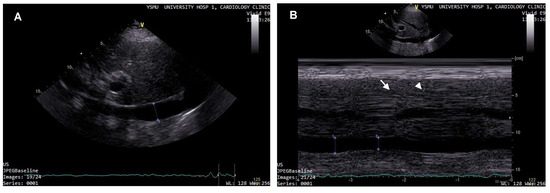

4. Lung Ultrasound

5. Right Ventricular HF Decompensation